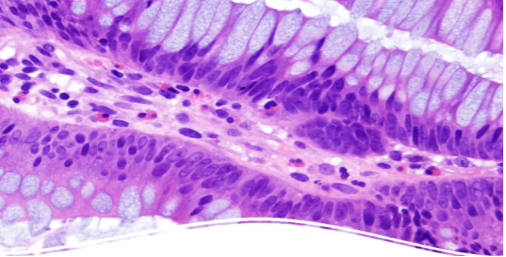

HE染色法

蘇木精—伊紅染色法(Hematoxylin-eosin Staining),簡稱HE染色法,是組織學、胚胎學、病理(lǐ)學教學與科研中最基本、使用最廣泛的技(jì)術(shù)方法。

蘇木精染液為(wèi)堿性,主要使細胞核內(nèi)的染色質與胞質內(nèi)的核糖體(tǐ)着紫藍(lán)色;伊紅為(wèi)酸性染料,主要使細胞質和(hé)細胞外基質中的成分着紅色。